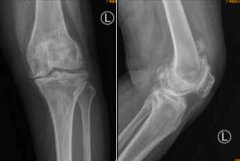

南都讯 记者李春花 通讯员 王慧 75岁的何阿姨,常年受到双膝关节疼痛的折磨,